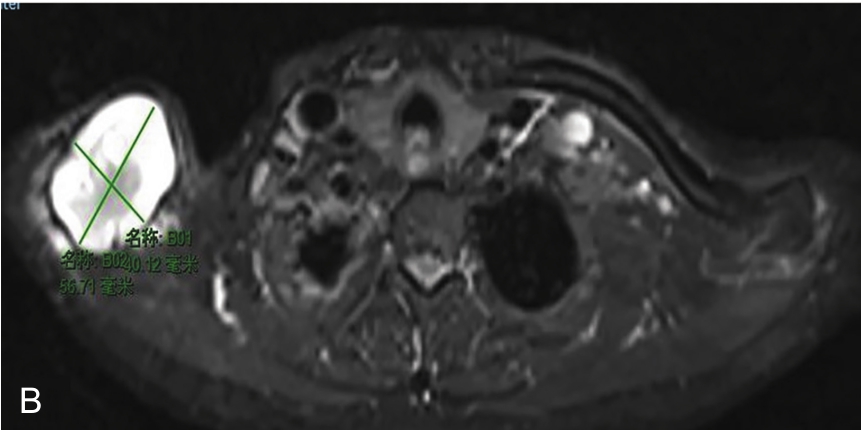

▲ 图2-1-12 超声引导下右侧肩关节周围滑膜囊肿穿刺治疗

A~B.患者肩关节MRI,星号及测量键:滑膜囊肿